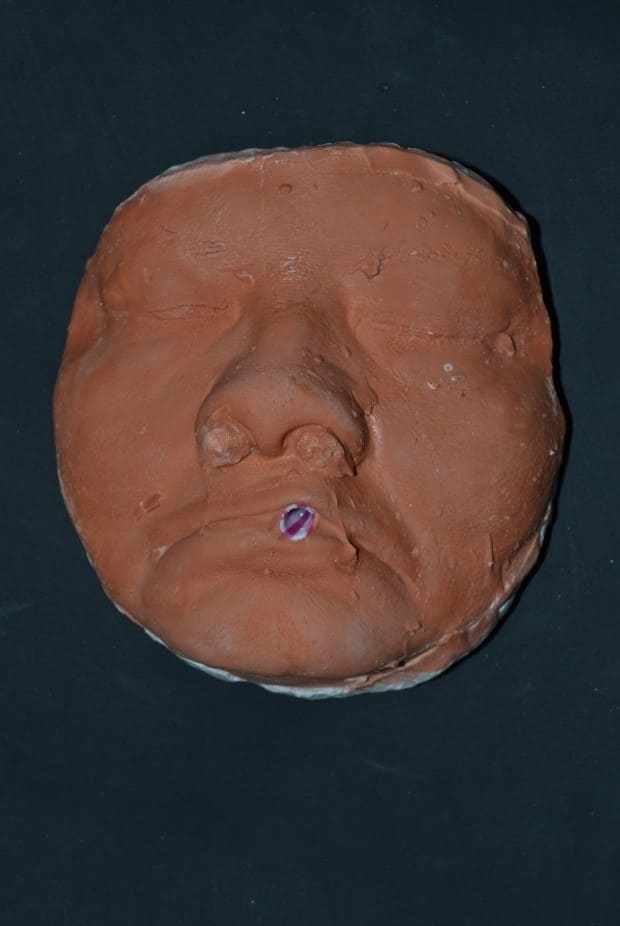

Thus, a new planning for rehabilitation was executed, having as a starting point the facial molding. The clinical sequence used was: skin cleansing by removing makeup and oiliness, protection of hair with bandage, application of solid vaseline in the facial hairs, tamponade of the nostols with cotton wool and a canudo for mouth breathing (figure 25). Then, the alginate (Jeltrate Dustless®, Dentsply, Argentina) was started using two parts, with the proportion of water/powder being 4:4. After being manipulated, it was deposited in small parts in the region to be molded with the aid of a spatula (figure 26), then the retention with cotton on the alginate was performed and the common plaster type II (Asfer®, Brazil) was added, in order to confer stiffness (figure 27), preventing deformation during its removal.

Figure 25: Preparation for the beginning of facial molding.

Figure 26: Alginate deposition on the face.

Figure 27: Insertion of plaster on the retention.

The mold was removed with slight movements, prompting the patient to move the mime muscles (figure 28). Immediately after molding, the mold was filled with type IV plaster (Durone®, Dentsply, Argentina) to obtain the facial model. With the aid of a vibrator, the plaster was deposited on the mold to prevent the formation of bubbles and when taking prey, the model was removed, so the finishes were executed (figure 29). Subsequent surgical removals, the treatment plan of choice was radiotherapy, being performed for two months, where it has already begun and is under medical follow-up.

Figure 28: Mold removed.

Figure 29: Model of the finished face.

Through histopathological examinations of the last surgeries performed on the patient, which indicated margin compromise, a more invasive surgery was planned by her physicians, which may compromise noble structures of facial support. Thus, facial molding was proposed, being as a guide for possible aesthetic-functional rehabilitation, after inavasive surgical procedure. The materials described in the literature for the preparation of facial molding are elastomers, hydrocolloides and plasters (AQUINO et al., 2012). The chosen technique is quite usual, low cost and easy execution, the material of choice for the case was irreversible hydrocolloside and plaster. Alsiyabi and Minsley (2006) mention that the conventional technique using irreversible hydrocolloide can result in inaccuracy and distortion of molding. Then, the authors propose the use of silicone, which will reduce clinical clothing and the fact that the material presents dimensional stability, deformation resistance and high tear resistance. On the other hand, the main disadvantage is the high cost of the material. Thus, facial molding performed with irreversible hydrocolloide proved to be effective, without distortions and low cost.